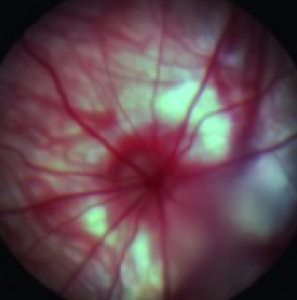

CBI provides special techniques including, OCT (See our OCT video), ERG, ocular ultrasound, gonioscopy, tonometry, laser photocoagulation, slit lamp, funduscopy, pachymetry, Schirmer test, phenol red thread test, hypoxic or hyperoxic chambers, retinal angiography, device implantation, lens removal or insertion, whole mount preparation, ocular histology and immunohistochemistry and ocular photography.

- Funduscopy and Angiography